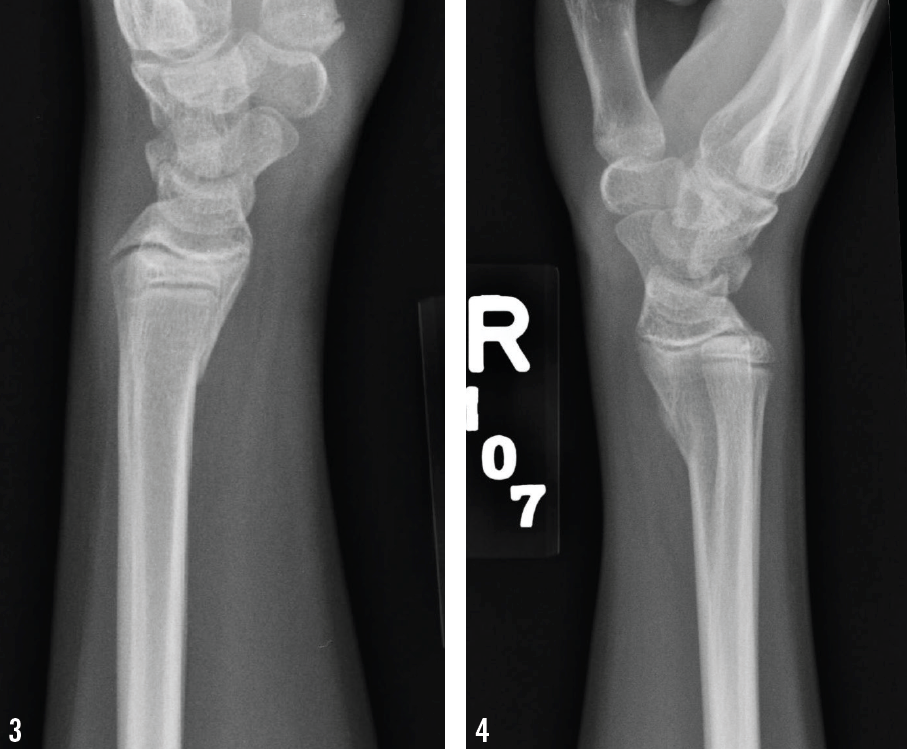

Anteroposterior radiographs are shown below.

Wrist radiographs revealed bilateral transverse fractures of both distal radii, with slight apex dorsal angulation on the right side (Figures 1-6). Both sides showed normal mineralization and slight age-appropriate openings at the epiphyses.